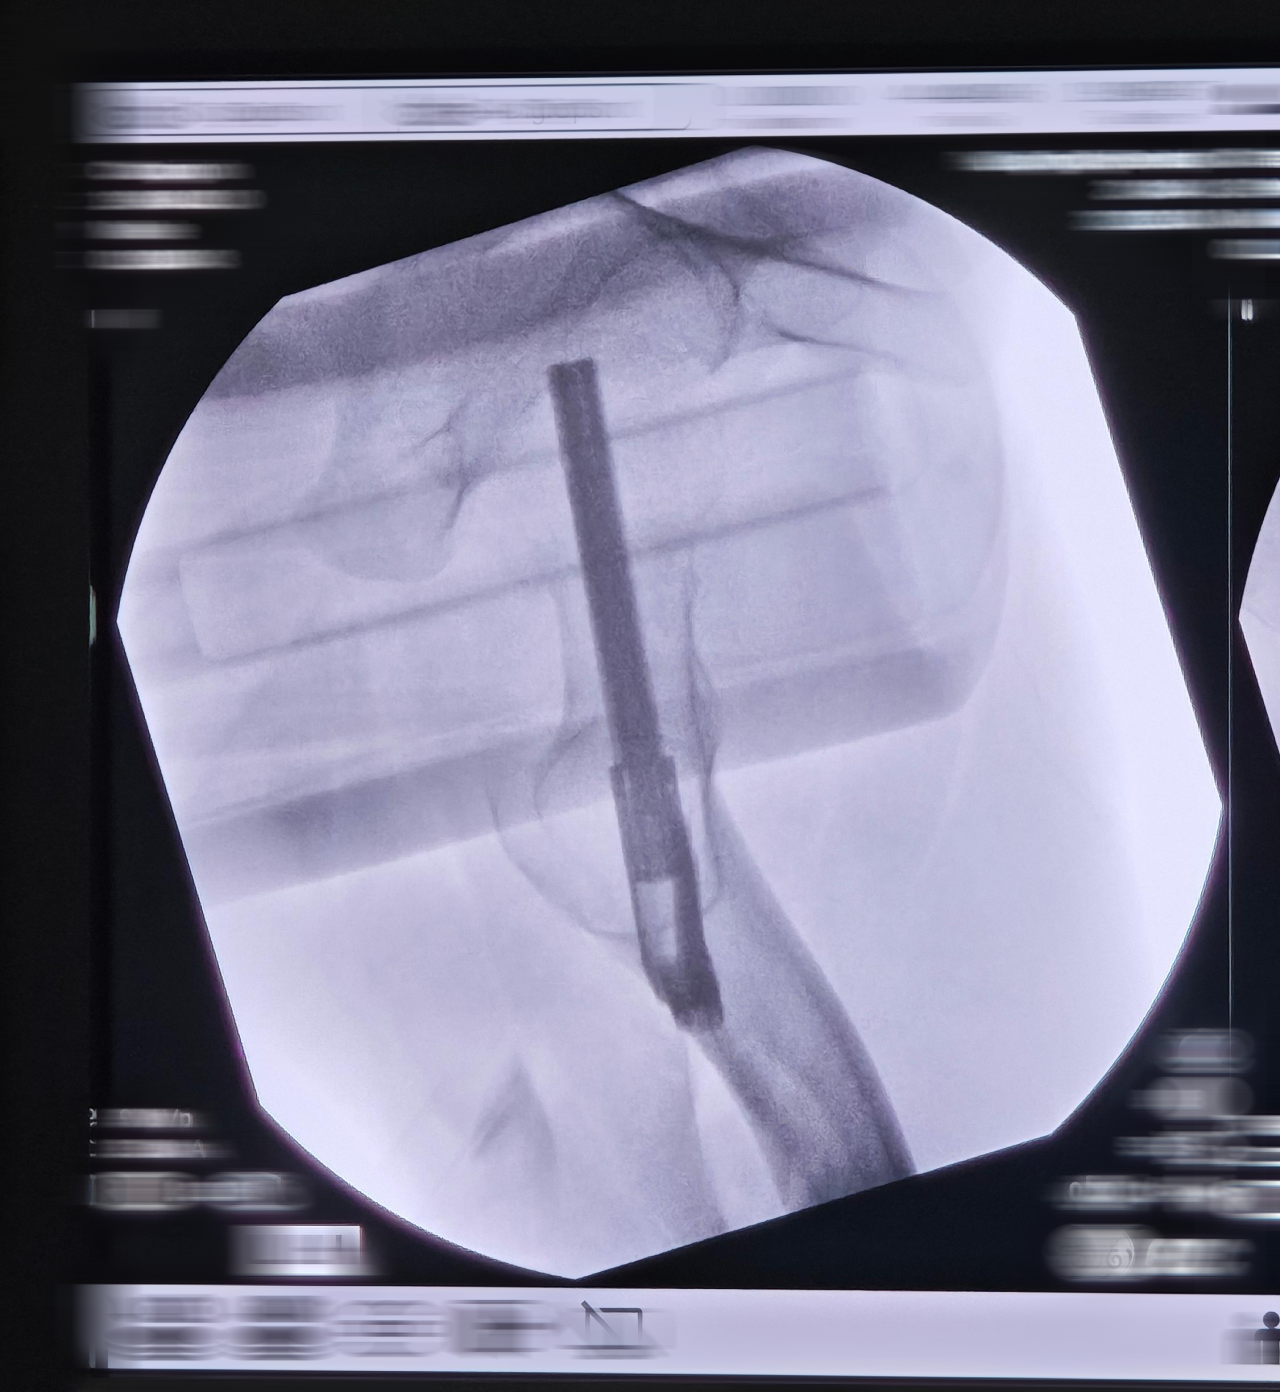

2.手术治疗:FNS股骨颈动力钉系统

FNS优势

更强抗旋效果:抗旋螺钉与固定钉相互锁定/且分叉(成角7.5°),有助于防止股骨头的旋转位移,相对于动力髋螺钉能够提供更好的防旋效果。

成角稳定:

板与固定钉之间成角稳定结构(130°颈干角),能够有效防止内翻塌陷和股骨颈短缩,相对于普通的中空螺钉治疗能够提供更充分的角稳定性。

术中主动加压/术后动力加压:固定钉和抗旋螺钉锁在一起,整体可动力加压,距离为20mm;外侧预留了足够空间,一定程度上避免外侧顶起引起的不适。

更小的植入物占位面积:

FNS对植入物尺寸进行了更小设计,允许小切口植入且外侧突出更少;植入物在骨面上的占位面积与三枚空心钉相似。